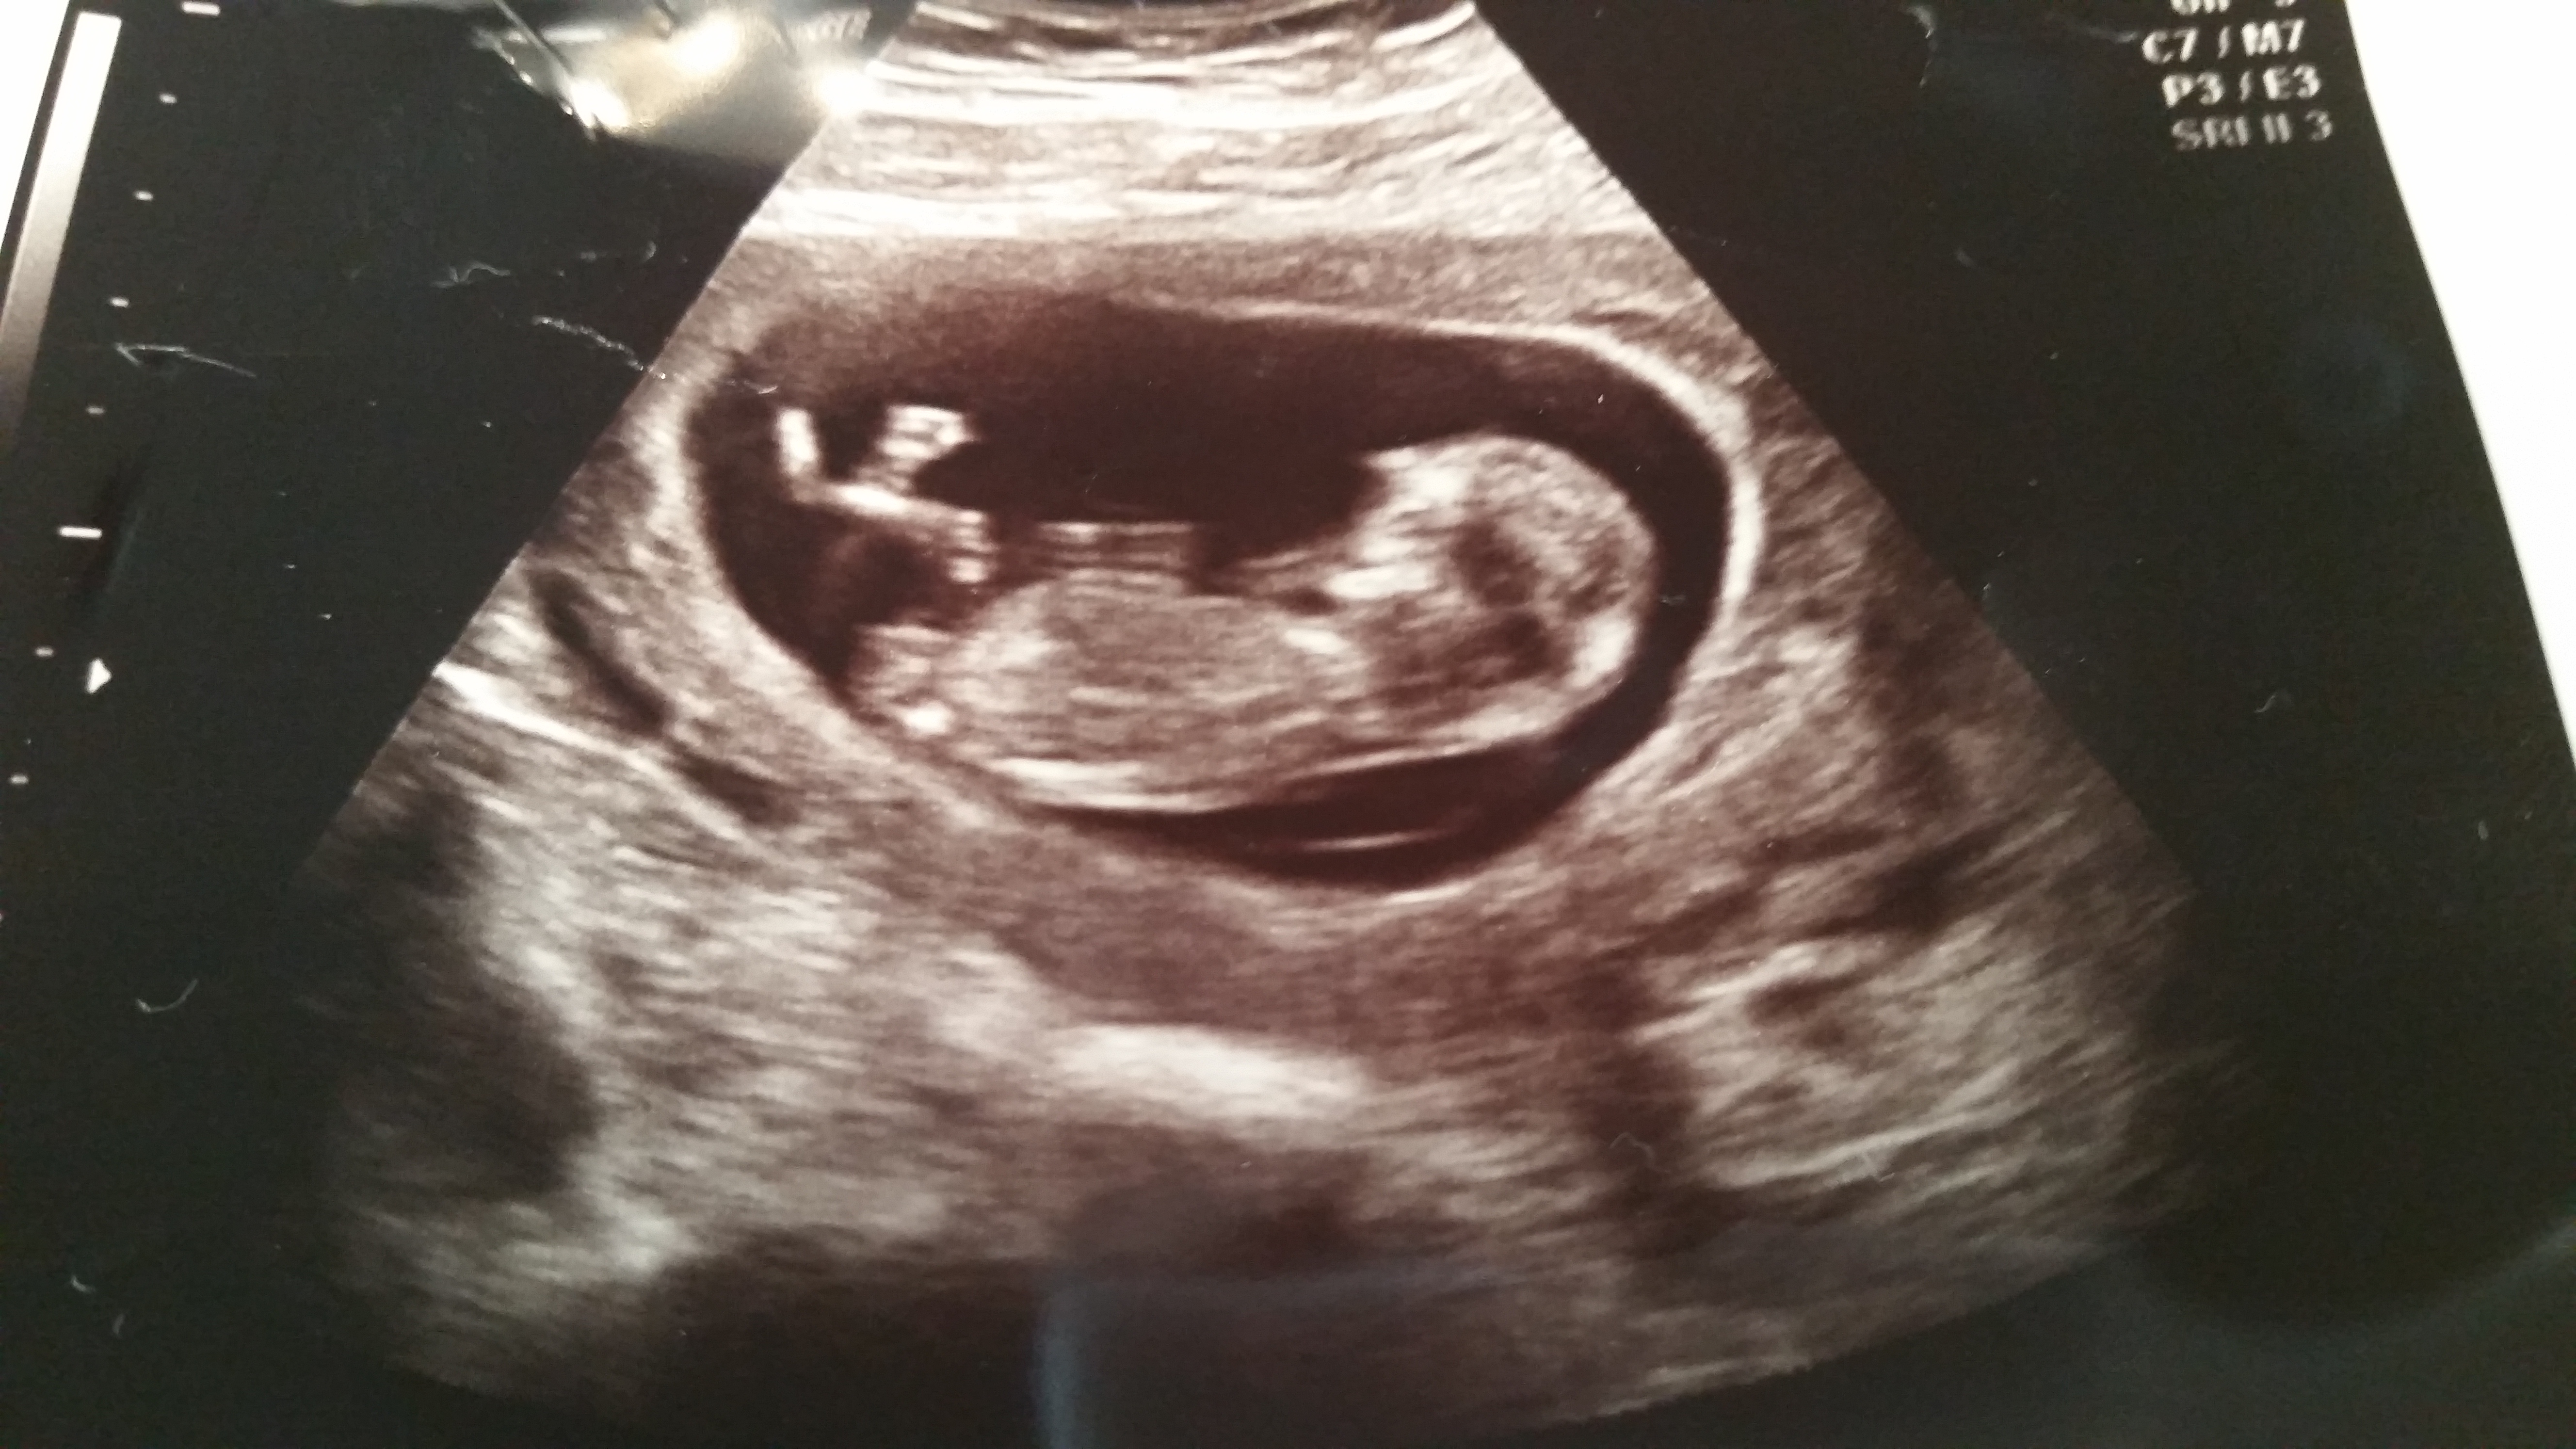

I sent my 'nub shot' in (see below) even though I was pretty certain it looked girl.  Here's what they had to say:

Your personalized results: From the picture you submitted, we find that the nub appears to be parallel and less than a 30 degree angle in relation to the spine. Without scanning for full effect, we cannot be certain there are male indicators, however, this is our most educated guess.

This was the one we sent to the gender experts and they said it was a boy but it's a little girl ♡♡♡